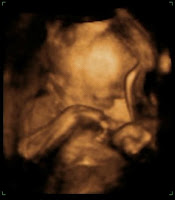

Quanto aos bebês, está tudo ótimo! E parece que realmente chegaremos em 34 semanas facilmente, e não deve haver nenhum motivo de nascerem antes, o que é excelente, esta era nossa meta desde sempre!!!